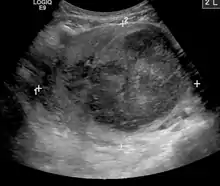

الفحص باليدين قادر على تحديد وجود الأورام كبيرة الحجم، يعد استخدام الموجات فوق الصوتية أداة التشخيص المثالية لتقدير وجود الورم. يصف التخطيط بالموجات الصوتية الورم على أنه كتل بؤرية غير متجانسة النسيج، والتي تؤدي إلى تظليل في الإشعاعات فوق الصوتية، ويمكن تحديد موقع وأبعاد الورم، كما يمكن استعمال التصوير بالرنين المغناطيسي لوصف الورم وأبعاده وموقعه في الرحم. طرق التصوير لا يمكنها التمييز بدقة بين الورم الخبيث والحميد، على الرغم من أن الورم الخبيث يعد نادرا. النمو السريع أو المفاجئ بعد انقطاع الطمث سوف يزيد الشك من وجود ورم خبيث في الرحم، وقد يكون هناك آثار غزو للأنسجة المحيطة. نادرا ما يتم أخذ خزعة للتشخيص، وإذا تم أخذها، فإنها لا تكون تشخيصية، واذا لم يكن هنالك تشخيص واضح بعد التصوير، يتم الإيعاز بالجراحة . ومن طرق التصوير الأخرى التي لها أهمية في تقييم الورم الذي يؤثر على التجويف الرحمي: تصوير الرحم وقنوات فالوب، والتصوير بالموجات الصوتية بعد ملئ الرحم بسائل .

ورم ليفي عضلي كبير جدا ( 9 سم )، والذي يسبب متلازمة احتقان الحوض كما يُرى في صورة الموجات فوق الصوتية.